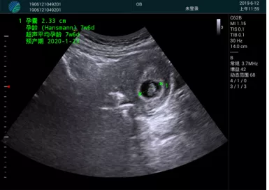

清晰顯示孕囊,通過軟件包計(jì)算孕齡7w+6d

M20實(shí)時(shí)引導(dǎo),術(shù)中清晰顯示孕囊被破壞和抽吸針的過程,清晰顯示吸引針

抽吸結(jié)束后縱切子宮,孕囊已被完全抽吸,未見明顯殘留

橫切子宮,發(fā)現(xiàn)右側(cè)宮腔靠近宮角處有少許脫模樣殘留

M20引導(dǎo)下,抽吸針找到右側(cè)宮角處再次清掃

二次抽吸后再次進(jìn)行超聲檢查,宮腔未見殘留,宮腔線清晰顯示

超聲引導(dǎo)下可視化人流是技術(shù)安全性的保障,一般對人流術(shù)設(shè)備預(yù)算不高,M20具備婦產(chǎn)科軟件包,且穿透力圖像質(zhì)量好,既滿足人流引導(dǎo)需要,也可用于床旁超聲的需求。